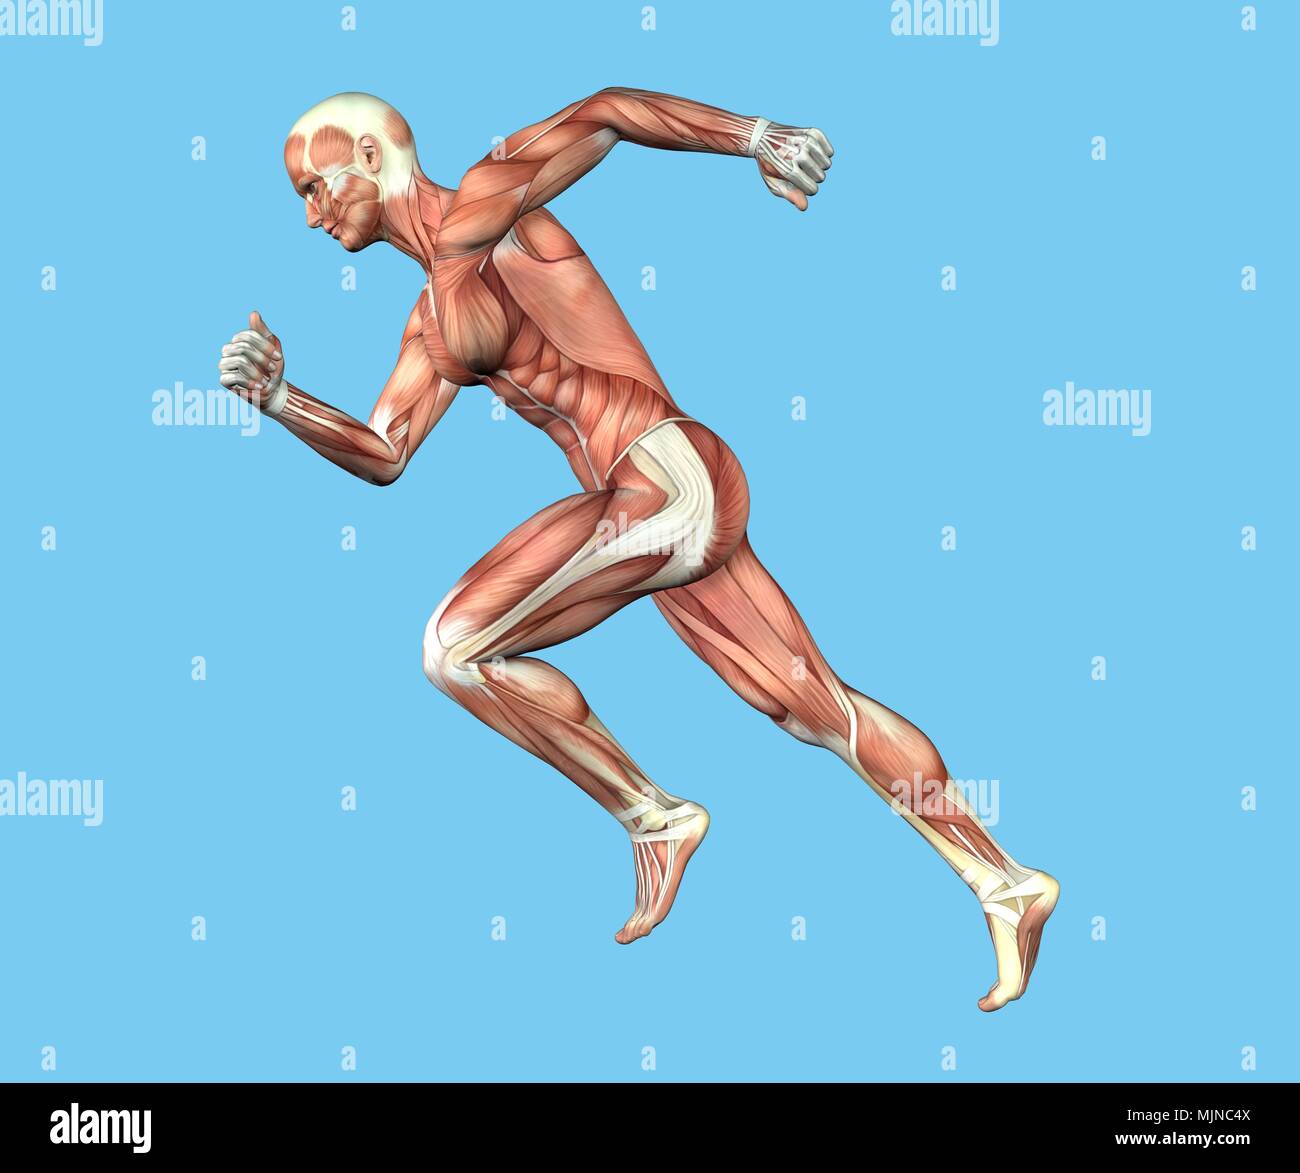

RMFX60TP–Menschen, Anatomie, Muskel, Körper, medizinische, Medizin, Illustration, Mann, Männlich, Gesundheit, muskulös, Wissenschaft, System, Biologie, Muskeln, ich

RF2A9AXYJ–Menschliche Körper Anatomie Muskeln Aufbau eines männlichen, Vorderansicht Seitenansicht und Perspektive, 3D-Rendering im Hintergrund